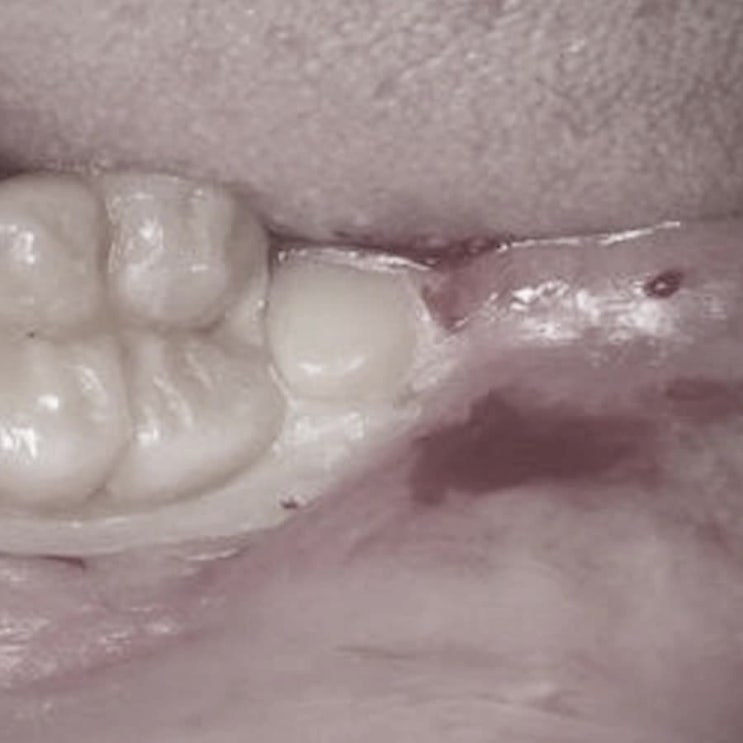

해안동사랑니발치 사전 검사로 주위염 여부를 체크

사랑니로 인해 흔하게 발생하는 잇몸 염증성 주위염 질환 치아 중 가장 마지막에 나오는 사랑니는 입안 끝 ...